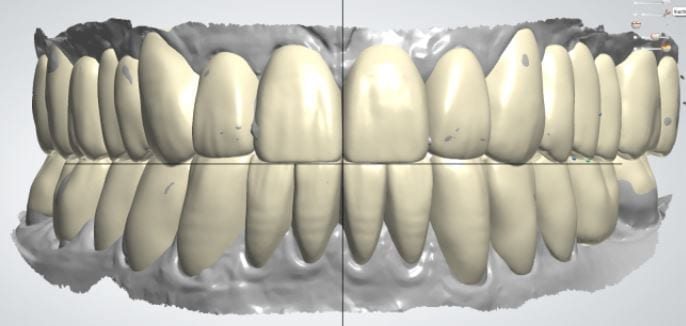

Once the appropriate library is chosen, the digital wax ups are performed. In the subsequent photos you can see the transparent overlay of the wax-ups to the original position of the existing dentition

Once the case is designed to the ideal vertical dimension then multiple shells can be fabricated for treatment. The wax up model can be uniformly reduced by .5mmm’s circumferentially and a temporary shell can be designed. Once the teeth are prepared, these shells can be relined and seated onto the preps.